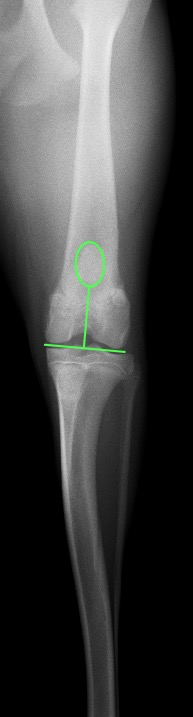

次の写真は右が術前の脱臼時、左が術後になります。

膝蓋骨が大腿骨の真ん中にしっかりと整復されているのが分かるかと思います。

今回の手術は通常のブロック型の滑車溝造溝術に近位側にウエッジ型の造溝術を加え、膝蓋骨が高い位置に来た場合でも脱臼しないようにしました。